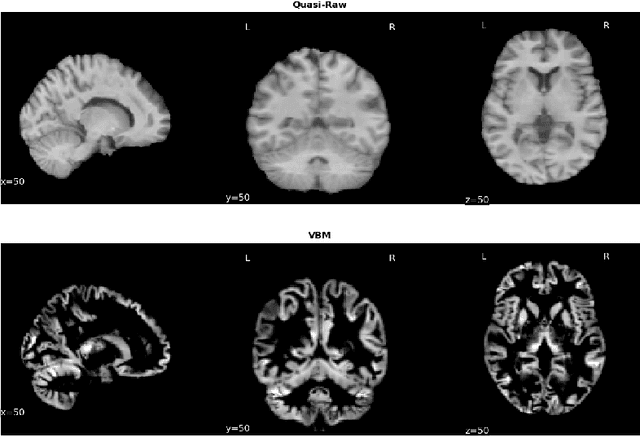

Abstract:Deep Learning (DL) and specifically CNN models have become a de facto method for a wide range of vision tasks, outperforming traditional machine learning (ML) methods. Consequently, they drew a lot of attention in the neuroimaging field in particular for phenotype prediction or computer-aided diagnosis. However, most of the current studies often deal with small single-site cohorts, along with a specific pre-processing pipeline and custom CNN architectures, which make them difficult to compare to. We propose an extensive benchmark of recent state-of-the-art (SOTA) 3D CNN, evaluating also the benefits of data augmentation and deep ensemble learning, on both Voxel-Based Morphometry (VBM) pre-processing and quasi-raw images. Experiments were conducted on a large multi-site 3D brain anatomical MRI data-set comprising N=10k scans on 3 challenging tasks: age prediction, sex classification, and schizophrenia diagnosis. We found that all models provide significantly better predictions with VBM images than quasi-raw data. This finding evolved as the training set approaches 10k samples where quasi-raw data almost reach the performance of VBM. Moreover, we showed that linear models perform comparably with SOTA CNN on VBM data. We also demonstrated that DenseNet and tiny-DenseNet, a lighter version that we proposed, provide a good compromise in terms of performance in all data regime. Therefore, we suggest to employ them as the architectures by default. Critically, we also showed that current CNN are still very biased towards the acquisition site, even when trained with N=10k multi-site images. In this context, VBM pre-processing provides an efficient way to limit this site effect. Surprisingly, we did not find any clear benefit from data augmentation techniques. Finally, we proved that deep ensemble learning is well suited to re-calibrate big CNN models without sacrificing performance.